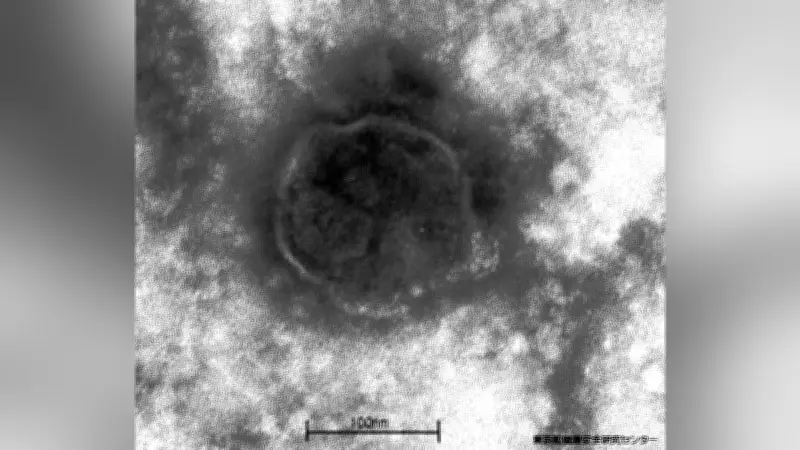

東京ではしか感染者が急増、今月だけで55人確認

東京都内で麻疹(はしか)の感染者が急増しており、今月だけで55人が確認されたことが明らかになった。都保健医療局によると、1月から今月13日までの速報値では、感染者数は合計109人に上る。このペースは、現在の集計方法が導入された2008年の年間1174人に次ぐもので、2011年の年間178人を上回る可能性が高いとされている。